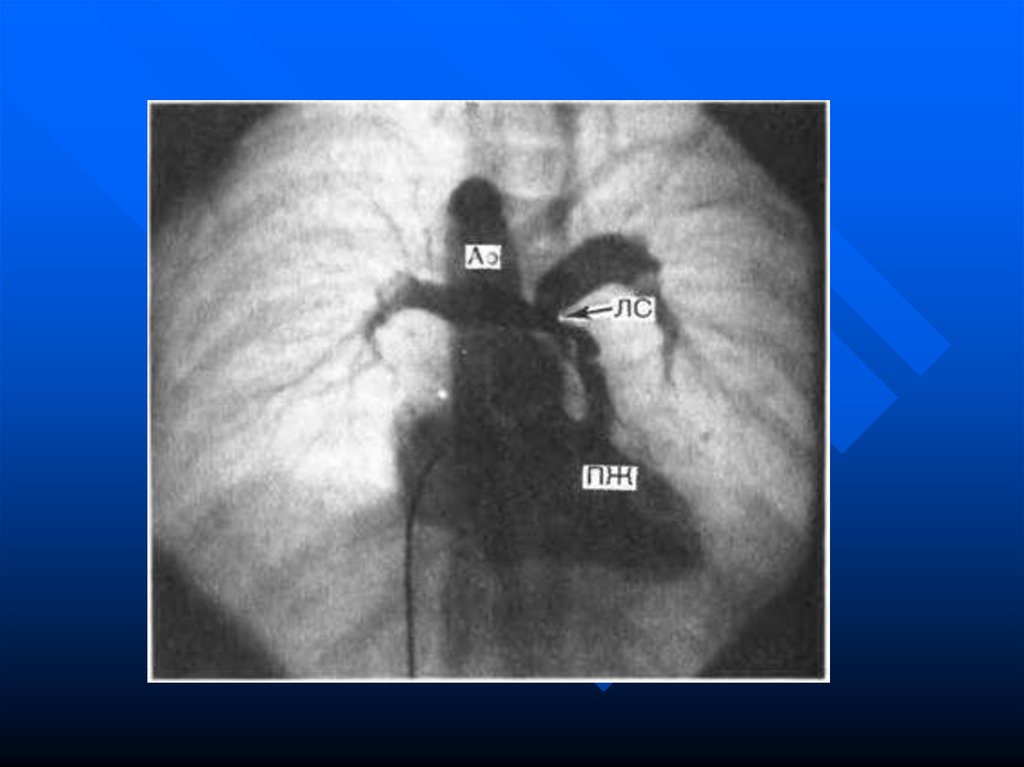

сосудов заканчивается на 7-8 неделях

гестационного возраста.